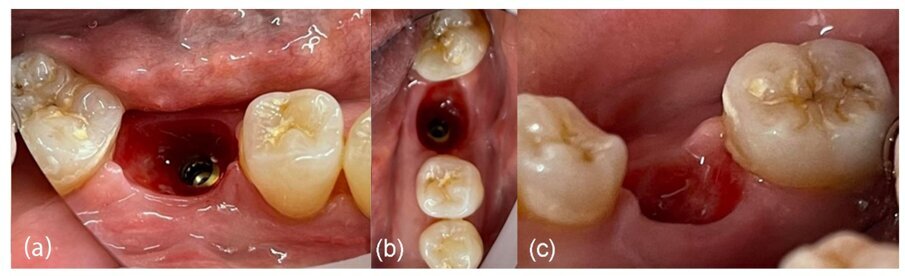

L’esame clinico al termine del periodo di guarigione di 4 mesi ha rivelato, dopo la rimozione del moncone anatomico e l’uso di una sonda parodontale (sonda Williams PW - Hu-Friedy Group), la generazione di un profilo cervicale adeguato (Fig. 22) con un’altezza del tessuto molle di 4 mm dalla piattaforma del moncone di connessione fino al margine del tessuto marginale sia sul lato vestibolare che sul lato linguale (Fig. 23). Tenendo conto che l’altezza del moncone di connessione era di 2 mm, la larghezza complessiva del complesso sopracrestale è stata valutata a 6 mm dalla piattaforma dell’impianto (Fig. 24). Il tessuto cheratinizzato è stato preservato sia sul lato vestibolare che sul lato linguale.

Rivalutazione clinica

Nel caso 2, il tessuto cheratinizzato è stato preservato anche sui lati vestibolare e linguale a T2 e i valori dell’altezza del complesso sovracrestale erano identici a quelli registrati nel caso 1 (Fig. 26). Per quanto riguarda la valutazione a T3 e dopo l’inserimento di una corona monolitica in zirconia completa a 4 mesi, è evidente che è stata preservata una mimica del profilo cervicale del tessuto molle con conservazione del tessuto cheratinizzato (Fig. 27). Infine, sono state effettuate impronte digitali intraorali utilizzando lo scanner intraorale iTero (Align Technology), a T1 e a T3. I file STL (standard tessellation language) sono stati esportati nel software DTX Studio Clinic (Envista) per la comparazione nel tempo. Sulla base di un algoritmo di informazioni reciproche, le scansioni sono state sovrapposte automaticamente e un codice a colori ha mostrato le aree di differenza (Fig. 27).

Fig. 26_Generazione del profilo cervicale a 4 mesi dopo la rimozione del moncone personalizzato: a) vista vestibolare, b) vista occlusale, c) vista linguale.

Fig. 27_Risultato clinico del sito 46 con corona in zirconia in situ dopo 2 anni e 7 mesi.